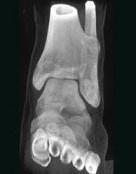

问题 女,35岁,左侧外踝可扪及一硬结,有轻压痛,请结合影像学检查,选出最可能的诊断()

选项 A.骨瘤 B.骨软骨瘤 C.骨巨细胞瘤 D.骨肉瘤 E.骨样骨瘤

答案 B